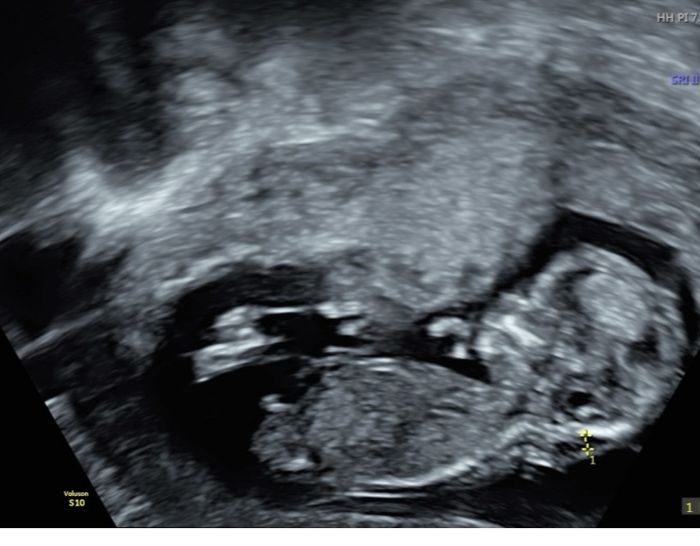

Ciao Sabrina! Non so se puoi aiutarmi perché credo che dalle immagini non si veda benissimo il tubercolo ma ecco sicuramente essendo più esperte di me può essere che mi sbaglio 🤣 ho fatto eco stamattina e in base alle sue misure dovrei essere 13+2 invece che 12+3. La ginecologa non è riuscita a sbilanciarsi, o meglio appena l’ha visto ha detto non saprei è ancora molto presto e può ancora cambiare, però così ti direi maschio. Poi appena ha cambiato posizione ha detto vedi in questa posizione ti avrei detto femmina. E in effetti in quella posizione si vedevano due lineette, mentre in altre un qualcosa che spunta 🤣 mi sono solo confusa di più le idee, ma comunque la mia sensazione è che sarà maschio. Ti lascio qualche eco espirando si capisca qualcosa Nub theory, giochiamo un po’ 4

In effetti dalla maggior parte delle eco sembra un maschietto. Solo in una ho il dubbio ma nelle altre il tubercolo mi sembra puntare molto in alto quindi in questo caso, direi maschietto anche io..

c’è anche una foto da sotto.. dove pare un maschietto a tutti gli effetti: altra possibilità sono i genitali gonfi per la femmina. Ma in quelle di profilo mi sembra puntare in su e se tracciò una linea tra tubercolo vescica e spina dorsale, l’angolo viene maschile. Fammi sapere!